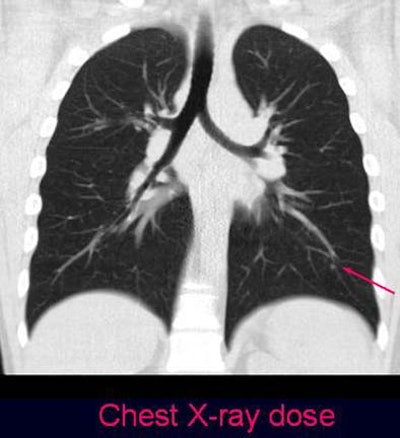

![]() |

| Coronal view of ultra-low-dose protocol reveals a solitary nodule in a 36-year-old patient with monolateral breast cancer (no histologic assessment was available). |

"Sometimes it's hard to distingush parenchymal nodules from pleural thickening," Romano explained. However, she added, most such findings would have been miscategorized using both protocols. Also, there were also a few artifacts (3-8, avgerage 3.21, mostly beam hardening), in the ultra-low-dose images, but they did not impede nodule detection significantly, she said.